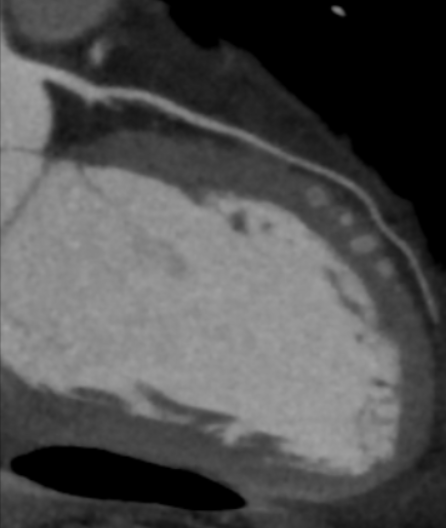

Διεξάγεται σε αξονικό τομογράφο πολλαπλών τομών (>128 detectors) με εξειδικευμένο λογισμικό απεικόνισης και επεξεργασίας των δεδομένων της παλλόμενης καρδιάς. Με την χρήση ακτίνων Χ, υπό ηλεκτροκαρδιογραφικό συντονισμό, διεξάγεται λήψη εγκάρσιων τομών της καρδιάς και με ειδική επεξεργασία δημιουργείται τρισδιάστατη εικόνα του καρδιακού μυ, των καρδιακών βαλβίδων και των στεφανιαίων αγγείων. Στον εξεταζόμενο χορηγείται σκιαγραφική ουσία που δίνει την δυνατότητα ανάδειξης στένωσης ή άλλων ανωμαλιών στις αρτηρίες.

Ακρογωνιαίος λίθος της διαγνωστικής αξίας της αξονικής στεφανιογραφίας είναι η δυνατότητα χαρακτηρισμού των αθηρωματικών πλακών (επασβεστωμένες, μικτής σύστασης, μη-επασβεστωμένες) ανάλογα με το ποσοστό εναπόθεσης ασβεστίου σε αυτές που καθοδηγεί την μετέπειτα κλινική απόφαση και θεραπεία.